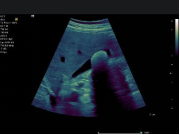

ACUSON Juniper 超声诊断系统的探头使用创新超低损耗透镜材料和微电子技术,实现高效性能和增加信号带宽,从而可获得优异的图像质量。西门子弹性成像 VTQ 声触诊组织定量技术,利用声脉冲辐射力(ARFI)原理,临床可用于间接无创检查肝组织硬度,进而区分肝纤维化过渡阶段;且是基于可视超声二维图像条件下进行定量分析,故其临床重复性好,得出高精度测量数据,测值单位 m/s 或 KPa 任意可选。西门子 VTQ 技术在慢性乙型和丙型肝炎纤维化的诊断和监测具有一定的意义。